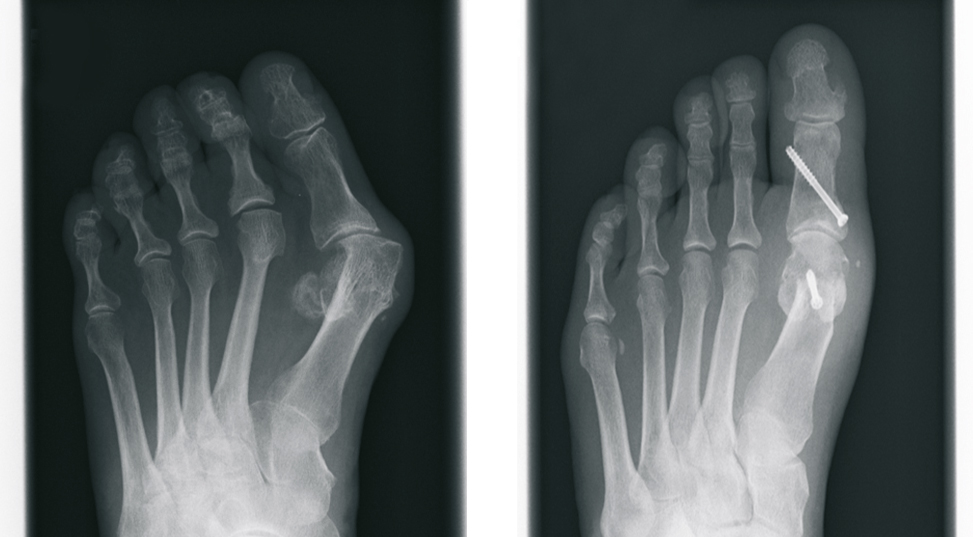

Beim Hallux valgus - im Sprachgebrauch häufig Ballenzehe genannt - handelt es sich um eine Abweichung der Großzehe nach außen, kleinzehenwärts. Diese Fehlstellung tritt häufiger bei Frauen auf. Die genaue Ursache ist nicht geklärt, sicherlich spielen falsches Schuhwerk und Erbanlagen eine große Rolle. Die unterschiedlichen Ausprägungen sind durch eine zunehmende Fehlstellung, verbunden mit Schmerzen, gekennzeichnet.

Von einer operativen Korrektur ohne Vorhandensein von Schmerzen, d. h. aus rein kosmetischer Sicht, ist abzuraten. Bei Auftreten von Schmerzen im Bereich der Großzehe ist die operative Vorgehensweise jedoch die einzig dauerhafte therapeutische Möglichkeit.

Nach ausführlicher Untersuchung, Betrachtung der individuellen Erfordernisse, sowie Analyse der Röntgenbilder wird die Behandlung festgelegt. Hierbei kommen verschiedene international anerkannte Operationsverfahren zur Anwendung. Wir verwenden dabei modernste Platten und Schrauben aus Titan.

In Abhängigkeit vom Ausmaß der Operation bzw. dem zur Anwendung kommenden Verfahren, haben wir die Möglichkeit sowohl eine ambulante, als auch eine stationäre Behandlung durchzuführen.